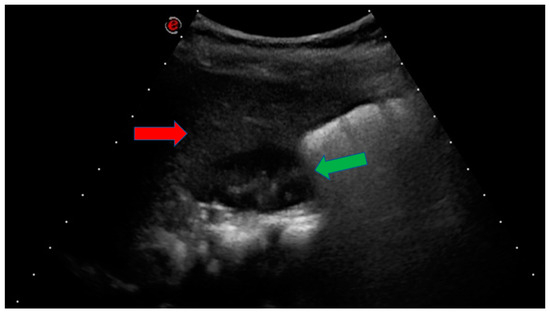

| Abdominal US | Liver hyperechogenic areas |

| Liver US | Steatosis | Normal in 3 subjects n.a. for the others |